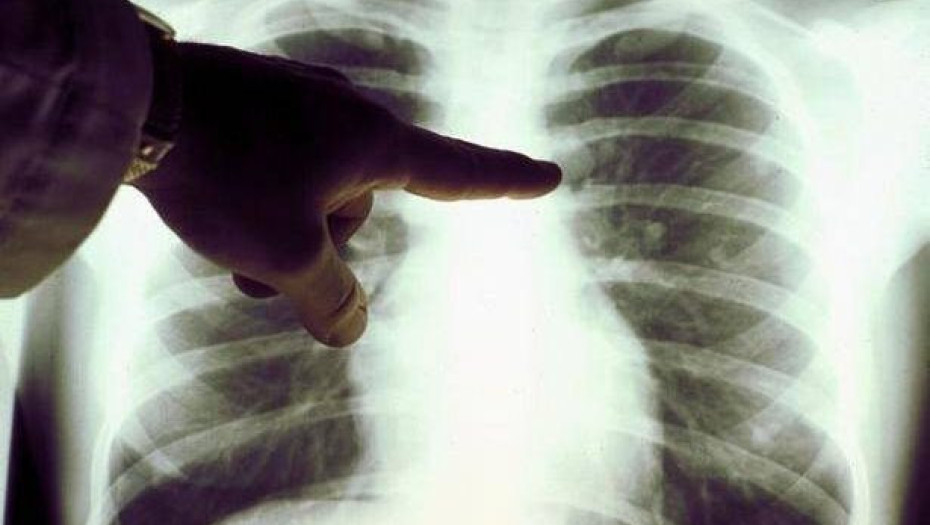

Πνευμονικό οίδημα: Τα σημάδια SOS που δείχνουν συσσώρευση υγρού στον πνεύμονα!

Πνευμονικό οίδημα είναι μια κατάσταση που προκαλείται από την περίσσεια υγρού στους πνεύμονες. Αυτό το υγρό συλλέγεται στους πολυάριθμους θύλακες αέρα στους πνεύμονες, καθιστώντας δύσκολη την αναπνοή.

Στις περισσότερες περιπτώσεις, το πνευμονικό οίδημα μπορεί να προκαλέσει καρδιακά προβλήματα. Αλλά υγρό στον πνεύμονα μπορεί να συσσωρευθεί και για άλλους λόγους, συμπεριλαμβανομένης της πνευμονίας, της έκθεσης σε ορισμένες τοξίνες, τραύματος στο θωρακικό τοίχωμα και την έντονη σωματική άσκηση ή ζουν σε μεγάλα υψόμετρα.